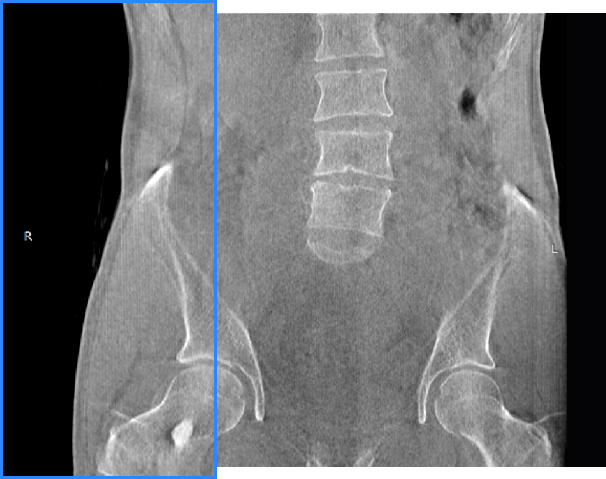

独特的负重位三维影像

填补常规CT/MR空白

• 髋关节

支持双腿或双侧髋关节扫描 | 方便对比,降低漏诊误诊

FOV 250mm

FOV 350mm